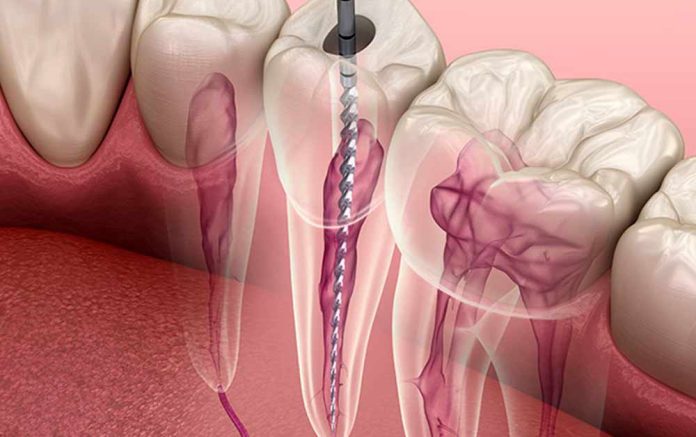

Kanal tedavisi nasıl olur diye soranlar için hemen cevaplayalım. Kanal tedavisi öncesinde hastanın dişi lokal anestezi kullanılarak uyuşturulur. Böylece hasta, tedavi esnasında herhangi bir yanma, batma, acı ya da rahatsızlık hissetmez. Dişin üstünde küçük bir delik açılır. Ardından diş sinirinin etrafındaki zarar görmüş ya da iltihaplı doku titizlikle çıkartılır. Diş kökünün kanalları özel aletlerle temizlenir. Dişin içindeki bakterilerden arındırılır. İkinci aşamada temizlenen boşluklar, diş ile uyumlu malzemelerle doldurulur ya da kaplama yapılır. Bu aşama sayesinde dişin doğal yapısı muhafaza edilmiş olur.